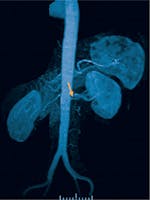

Stenoza de artere renale - Cauze, simptome și tratament

Stenoza de arteră renală este responsabilă de aproximativ 10% dintre cazurile de hipertensiune severă, refractară la tratamentul medicamentos.